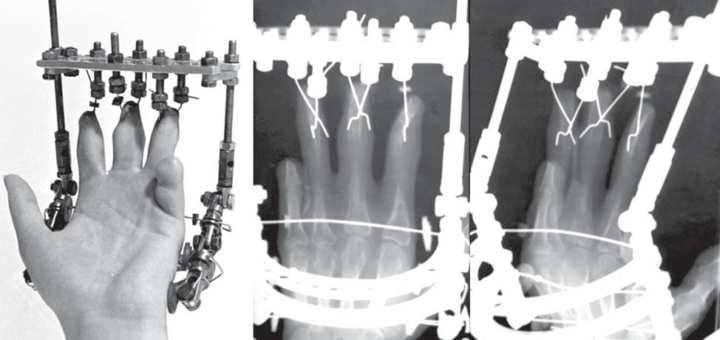

History of the Ilizarovs wire-fixator, stages of hand surgery development at the Ilizarov Center

© Shevtsov V.I., Kirienko A.P., Shikhaleva N.G., Novikov K.I., 2021 DOI 10.18019/1028-4427-2021-27-3-299-306 V.I. Shevtsov1, A.P. Kirienko2, N.G. Shikhaleva1, K.I. Novikov1 1Ilizarov National Medical Research Centre for Traumatology and Orthopedics, Kurgan, Russian Federation 2Humanitas Clinical...